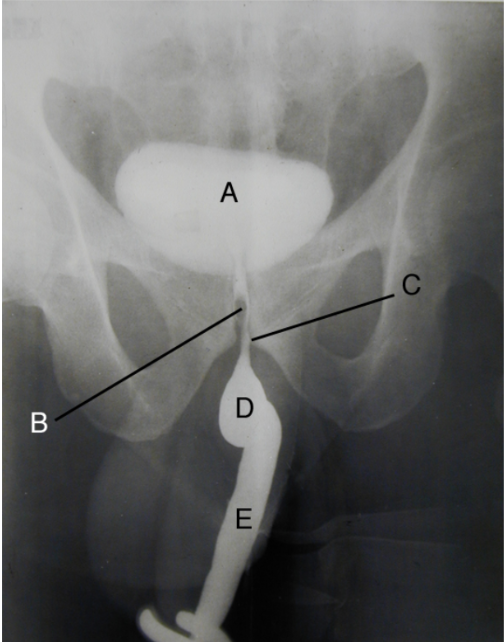

a. vesica urinaria

b. pars prostatica urethrae

c. pars membranacea urethrae

d. pars bulbosa urethrae

e. pars spongiosa urethrae